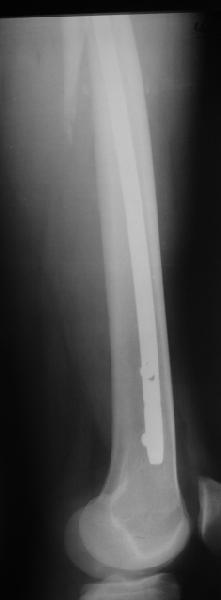

Как раз недавно у меня был примерный случай: больному 36 лет, поступил ночью, травма в результате мотоциклетной аварии, кроме чрезвертельного и спирального перелома левого бедра имеется переломы костей предплечья с этой же стороны. Скелетное вытяжение, а на следующий день больной про оперирован на ортопедическом столе с дистракцией. Чтобы не расколоть чрезвертельный перелом провели временную спицу ближе к переднему кортексу, из малого разреза костодержатель для репозиции, а фиксацию провели антиградным штифтом. Этапы операции на снимках.

Да, сейчас это и у нас самый напрашивающийся выбор. Сделали гвоздем ChM, картинки в приложении.